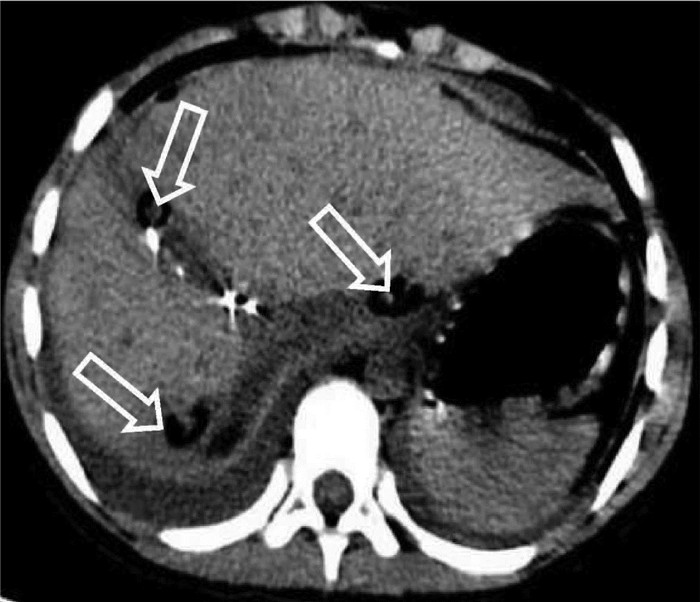

肝脏遗传性出血性毛细血管扩张症1例报告

王婷婷, 马亮, 陈建平

2022, 38(2): 423-425. DOI: 10.3969/j.issn.1001-5256.2022.02.032

摘要(1117) HTML (367) PDF (2696KB)(56)

摘要: